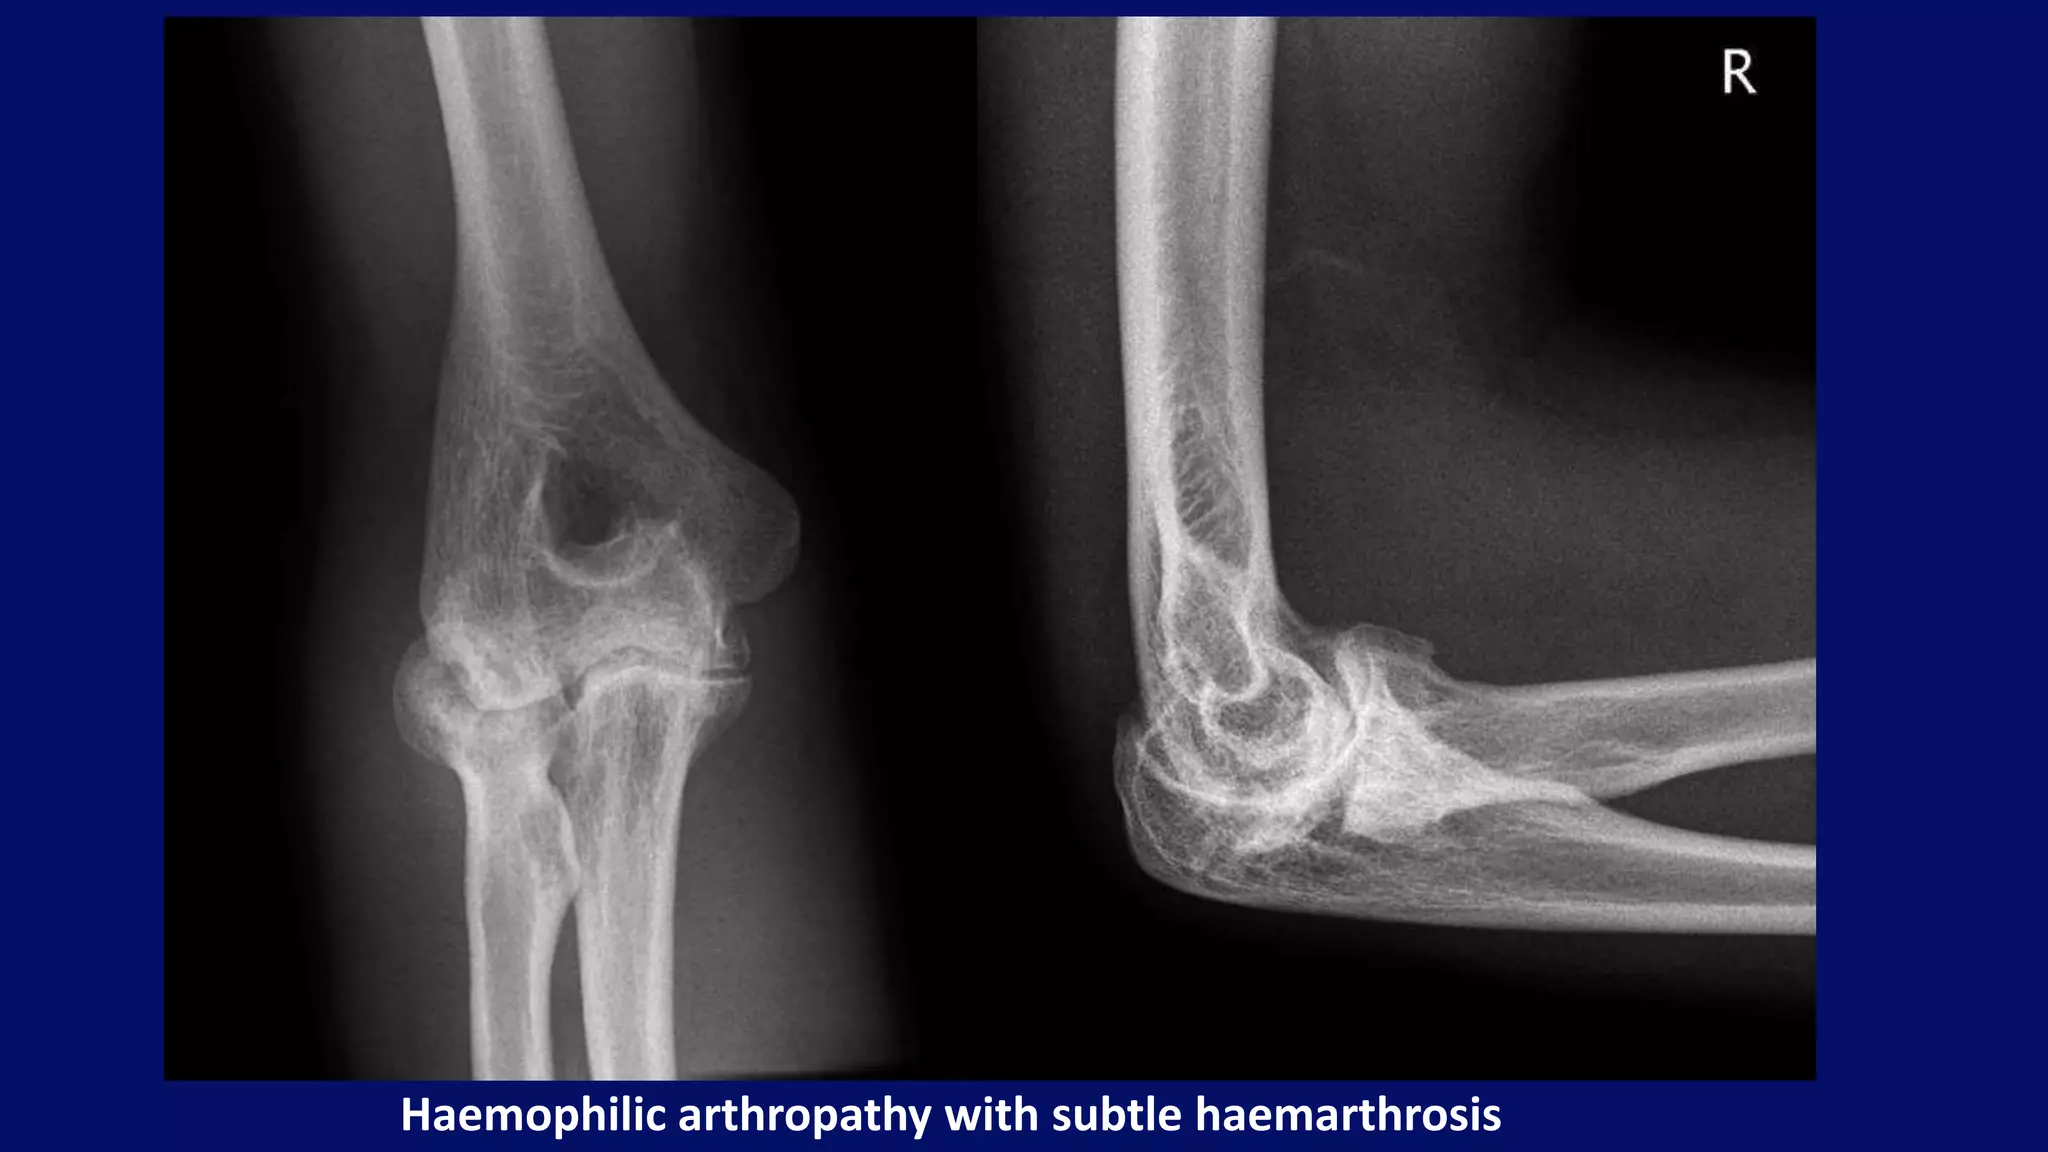

Hemophilia

• group of disorders characterised by a tendency to bleed as a result

of deficient clotting factors

• deficiency of factor VIII (haemophilia A) or factor IX

• arthropathy is a consequence of recurrent bleeds into joints

• knees, elbows, hips and ankles are most commonly affected

Radiographic features

• widened intercondylar femoral notch

• squared inferior margin of the patella

• haemophilic pseudotumours

• periarticular erosions

• features of osteoarthritis

Widened intercondylar notch with joint effusion

Haemophilic arthropathy with subtle haemarthrosis

• #119 Radiographs showing some of the features of haemophilic arthropathy in this patient with haemophilia. There is epiphyseal enlargement of the radial head, loss of joint space and a subtle haemarthrosis indicated by displacement of the posterior fat pad.